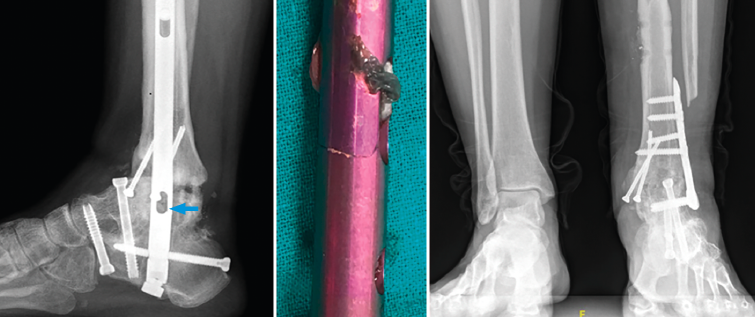

Figura 6. Imagen radiográfica y clínica en la que se aprecia la rotura parcial del clavo. Rescate con placa tibiotalar en proyección radiográfica en carga.

En este caso, la extracción fue sencilla: una vez retirados los tornillos de bloqueo, se realizó, con el sistema extractor del clavo, la extracción del mismo sin dificultad, ya que se trataba de una rotura incompleta. Realizamos un nuevo legrado de las superficies óseas, perforación de las mismas, nuevo aporte de injerto de cresta ilíaca y fijación con placa de artrodesis tibiotalar (Palex Medical), ya que la articulación subtalar estaba consolidada (Figura 6).